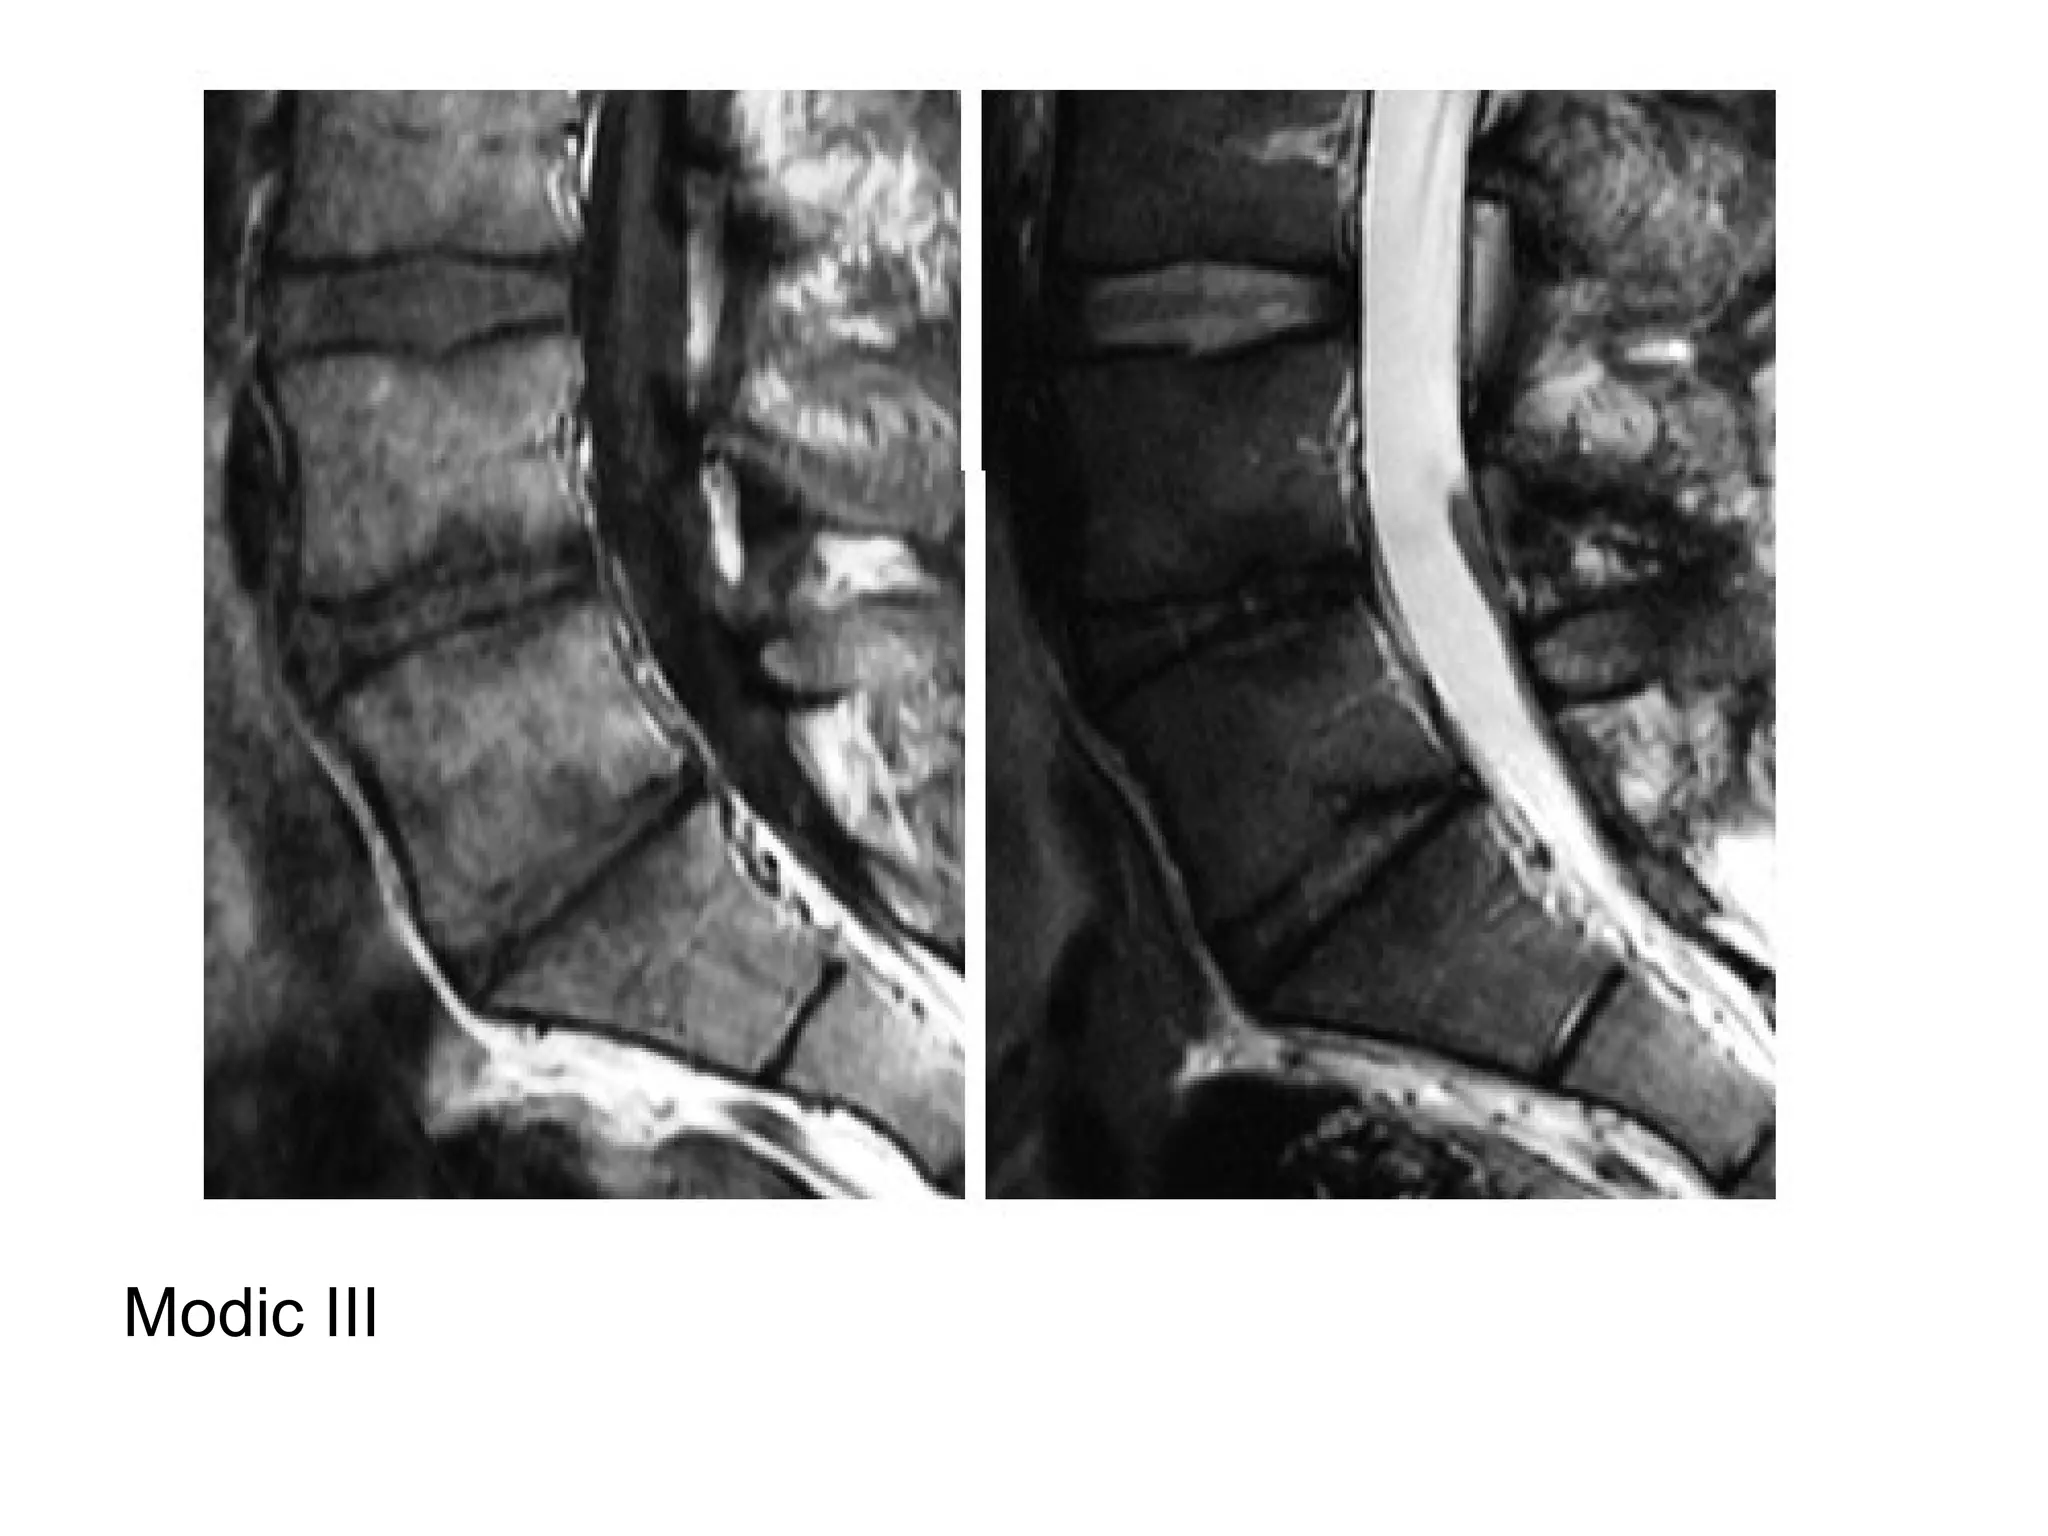

a) Modic I : dark T1 / bright T2 (vascular tissue

c) Modic III : dark T1 / dark T2 (sclerosis)

Modic , T1 & T2

Modic III